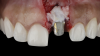

(3.) The crown was removed, and a partial thickness flap was reflected using a papilla-sparing incision design, which revealed that the implant was positioned too far facially and that its body was visible through a very thin layer of bone.

Figure 3

(4.) The crown was removed, and a partial thickness flap was reflected using a papilla-sparing incision design, which revealed that the implant was positioned too far facially and that its body was visible through a very thin layer of bone.

Figure 4

The patient in this case had undergone implant therapy at the site of tooth No. 9 and was restored with a cement-retained restoration more than 5 years prior. At presentation, the site demonstrated a peri-implant soft-tissue dehiscence that extended approximately 3-mm apical to the gingival margin of tooth No. 8. Thin and erythematous marginal tissue was evident at the zenith (Figure 2). The crown was removed, and a partial thickness flap was reflected using a papilla-sparing incision design. This revealed that the implant was positioned too far facially and that its body was visible through a very thin layer of bone (Figure 3 and Figure 4). The first objective of treatment was to minimize the facial extent of the emerging abutment and crown. To accomplish this, the facially positioned abutment and implant crown margin were both recontoured. The second treatment objective was to provide additional supracrestal soft tissue that would more adequately maintain the peri-implant margin. The tuberosity was selected as a donor site due to its dense, high-quality connective tissue, low propensity for shrinkage, and association with minimal patient discomfort. Once the graft was secured (Figure 5 through Figure 7), the flap was coronally positioned (Figure 8). After a healing period of 2 weeks, the margin of tooth No. 9 exhibited an ideal position in relation to its contralateral counterpart and demonstrated increased soft tissue thickness (Figure 9). Three months postoperatively, further healing had improved the esthetics and the position of the margin had been maintained (Figure 10).